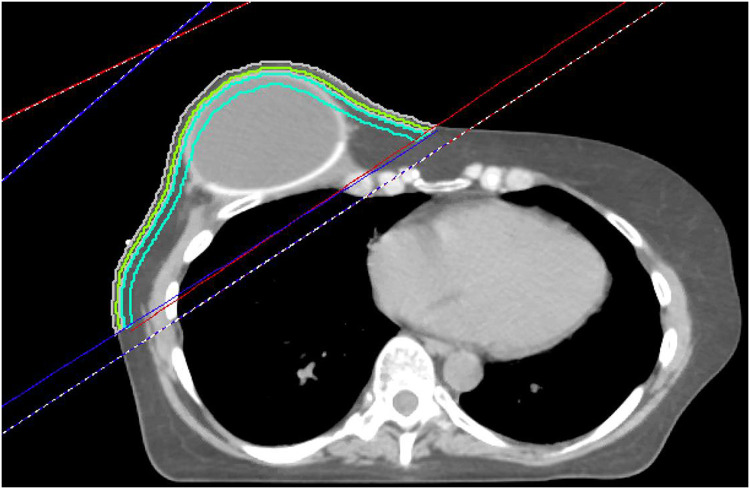

Composite PMRT plans, inclusive of any sequential scar boost administered, were reviewed on Pinnacle Version 16.2.1 (Phillips Medical Systems, Fitchburg, WI) for all patients for whom treatment plan dosimetry was available for review. For these patients, automated contours were created to generate 3 near-surface volumes for analysis of near-surface dose, comprising the volumes bound by the chest wall tangent beam and limited to 0 to 3 mm from skin surface (SR3), 0 to 5 mm from skin surface (SR5), and 5 to 10 mm from skin surface (SR10) (Fig. 1). These structures were confined to the tangent beams covering the chest wall, even when the beam's edge crossed midline to include the skin of the contralateral chest wall. The inframammary fold and skin overlying the axilla were encompassed within the near-surface skin contours. When VMAT was delivered, a similar approach was taken to generate these structures using the unopposed tangent beams from a conventional comparison plan. After generation of SR3, SR5, and SR10, dose-volume histogram data were exported for statistical analysis. During the years that this study cohort was treated, it was our institutional practice to offer daily bolus for patients undergoing PMRT, with potential removal of bolus after observing brisk chest wall erythema. Before export, recalculations were retrospectively performed for treatment plans that had not already accounted for any documented midtreatment bolus prescription modifications to reflect dose with bolus as delivered.

Figure 1.

Representative axial slice of a patient with a right-sided implant postreconstruction.

The red lines represent the medial beam edges, and the blue lines represent the lateral beam edges. The 3 skin rind structures are shown. Lime green represents 0 to 3 mm (SR3), gray represents 0 to 5 mm (SR5), and turquoise represents the 5 to 10 mm rind (SR10). The rinds extend to cover all tissue within the tangent fields, but do not extend into the supraclavicular field.